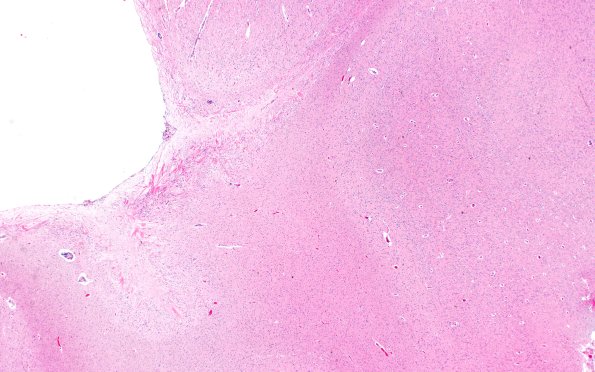

Washington University Experience | BASIC PROCESSES | Astrocytes & Astrocytosis | Astrocytosis | 11A1 Cerebral Palsy (Case 23) 2X H&E

A 32 year-old man with a medical history of congenital aqueductal stenosis status-post shunt placement at 3 days of life, complicated by several shunt revisions throughout his life, in addition to developmental delay, autism, and cerebral palsy, ---- 11A1-3 The walls of the lateral ventricle in this patient showing "wheat sheaving" reflecting astrocytosis. (H&E)